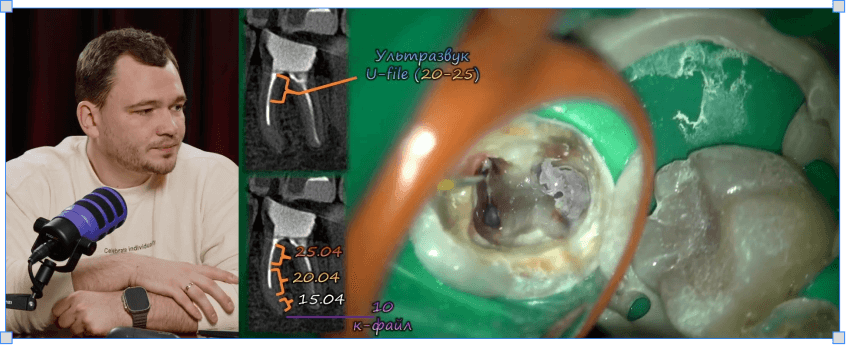

Микола Сорухан

Повторна ендодонтія

4 модулі

3 години

Все про штифти і розпломбування при повторному ендо

Протоколи вилучення уламків зламаних інструментів

Протоколи роботи зі сходинками і перфораціями в каналах